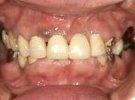

歯がこのままではダメだと思い、一念発起された50代女性の方です。

もちろん治療期間が長期にかかることも、治療費が高額になることも、外科的な手術が何度か必要であることなど、

インプラント治療と咬み合わせ治療のほぼ全てを大名歯科ホームページで予め知っていただいた上で決心され来院されたそうです。

インプラント治療は顎骨が乏しかったため、増骨手術も併用しなければならない難症例でした。

治療期間中は残存歯数が少ない上に、丈夫でないため生活に不自由な点がでました。

さらに咬み合わせが安定しにくい症例のため、プラスチック仮歯がよく壊れたり、外れたりして、修理に来院していただくなど大変な苦労とご迷惑をおかけしました。

審美性(見た目)は十分回復できたと思っており、患者さんも大変満足されています。

食事は当然のことかもしれませんが、よく咬めるようになったそうです。

咬み合わせ治療は非常に難しいため、これで十分かどうか分かりませんが現在もこのまま定期的なメインテナンス中です。